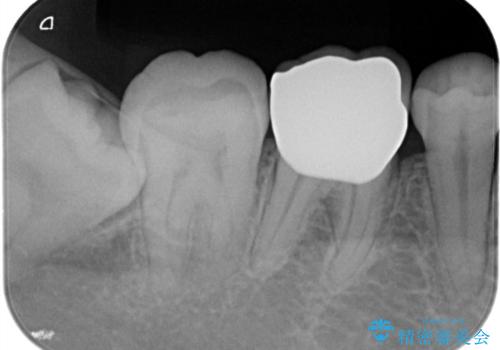

【オールセラミッククラウン】存在感のある銀歯を外したい

- 他院で矯正終了後、保定観察中の患者様が銀歯を白くしたいという主訴で来院されました。

オールセラミッククラウン(st)にて治療を行なっております。

オールセラミッククラウン(st)は

ジルコニアフレームに色調の再現がしやすいポーセレンを焼き付けた構造の被せ物です。